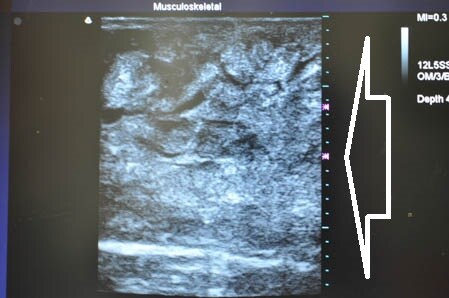

まずはいつものように

3Dタッチビュー(超音波画像)から見てみましょう。

白い矢印部分が皮下脂肪層です。

上腹部から。

↓ ↓ ↓